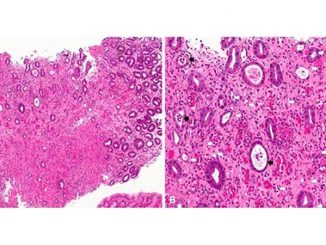

Mixed Results for Drug in Eosinophilic Gastritis

TOPLINE: Benralizumab, an eosinophil-depleting monoclonal antibody, induces histologic remission in patients with eosinophilic gastritis, but persistence of other disease features […]